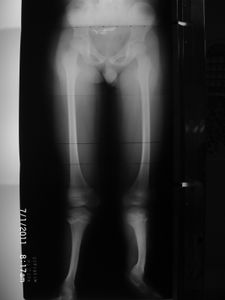

Meu nome é Pedro, tenho 24 anos e sou portador de uma deficiência rara nas duas pernas, chamada: Hemimelia Fibular Bilateral Grau 3.

Minha deficiência foi descoberta no 5º mês de gestação e desde os 2 anos de idade eu comecei a realizar cirurgias nas pernas. Por se tratar de uma condição rara (1 a cada 100 mil pessoas) não existe uma cura, pois minhas pernas não possuem todos os ossos, ligamentos e tendões necessários, mas há um tratamento, realizado com o ilizarov, que venho fazendo desde 2012.

Sendo assim, optei por vir aqui pedir ajuda para arrecadar dinheiro e tentar comprar o material cirúrgico para realizar a cirurgia e avançar mais um pouco nessa reta final, até agora eu já passei por 29 cirurgias nas pernas, algumas delas realizadas num período muito curto de meses, mas sempre com o convênio médico estrapolando o prazo permitido para liberar a cirurgia (que é 21 dias úteis). Dessa vez não está sendo diferente, já se passou o prazo e até agora nada, isso é muito frustrante pois além de lidar com a dor física do tratamento, é necessário lidar com a angústia de uma espera que não tem data para acabar.